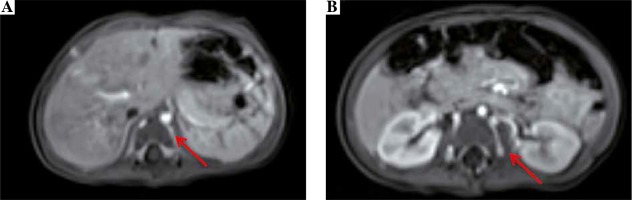

We present a case of a female infant born from second pregnancy (first pregnancy resulted in miscarriage in 20th week of gestation after abdominal injury), mother of Latin American descent, father of Polish origin. Negative family history of kidney diseases, calcium and phosphate homeostasis disorders, urolithiasis, systemic diseases, and thrombosis. The pregnancy was complicated by hypothyroidism, uterine myoma, urinary tract infections, and appendectomy at 16th week of gestation. Fetal ultrasound scan (US) performed repeatedly did not show any abnormalities, with normal image of the kidneys. The baby was born by caesarean section due to pre-labor rupture of the membranes, with a body weight of 3,570 γ and Apgar score of 10. The adaptation period was normal; the girl was vaccinated according to routine vaccination schedule and breastfed. At the age of 2 months, she was hospitalized in the city hospital due to bronchiolitis. The abdominal US showed kidneys 45 mm long with an abnormal image of the renal columns, with numerous hyperechogenic foci. Nephrocalcinosis was suspected and the infant was referred to our hospital. The girl was admitted at the age of 3 months in good general condition, no physical abnormalities, and arterial blood pressure of 77/36 mm Hg. Laboratory examination were as follows (reference ranges in brackets): WBC 8.06 × 103/µl (5.7-17), RBC 4.09 × 106/µl (3.2-4.3), PLT 415 × 103/µl (250-550), CRP < 0.5 mg/dl (≤ 1.0), creatinine 0.2 mg/dl (0.2-0.4), urea 14.0 mg/dl (2.2-27.8), calcium 10.5 mg/dl (7.7-11.5), phosphorus 7.2 mg/dl (2.5-7.0), alkaline phosphatase 281 U/l (80-345), 25(OH)D 20.4 ng/ml (20-50), parathyroid hormone 7.7 pg/ml (12-95); urinary crystallization ratio: calcium : creatinine ratio 0.43 (< 0.81), phosphorus : creatinine ratio 0.85 (0.3-1.2), magnesium : creatinine ratio 0.55 (> 0.1), magnesium : calcium ratio 1.29 (0.8-1.3). The results of urinalysis were within the normal range. In the ultrasound scan, numerous hyperechogenic foci in both kidneys were observed and nephrocalcinosis was suspected. Vitamin D3 supplementation was discontinued. After 3 months, serum phosphorus normalized (6.0 mg/dl), and 25(OH)D level was slightly below normal range (19.8 ng/ml). US showed right kidney 54 mm long, left kidney 62 mm long, linear calcifications along the pyramids visible in both kidneys, more lesions in the left kidney (Figs. 1A, 1B, 1D). Doppler scan showed lack of visible blood flow from the renal veins to IVC, with compensatory flow from the renal veins to the paravertebral plexuses; IVC obliteration, with a massive calcification in the hepatic section (Fig. 1C); minor linear calcifications in the liver caudate lobe at the point of contact with IVC. The connection between IVC and common iliac veins were not visible. The image suggested the history of extensive venous thrombosis. Magnetic resonance (MR) revealed no contrast flow in the iliac veins and IVC, compensatory venous outflow from the lower limbs and from the kidneys to the paravertebral plexuses (Fig. 2); in IVC, a segmental dilatation of 11 × 7 mm over a length of 23 mm spatially coincident with calcification described in the ultrasound scan. The results of coagulation system were as follows: INR 1.01 (0.9-1.2), kaolin-cephalin clotting time 34.62 s (28-40), fibrinogen 1.77 g/l (1.80-3.50), homocysteine 6.92 µmol/l (3.70-13.90), antithrombin III 96.3% (75-125), protein C 61% (50-125), protein S 67.36% (50-125), D-dimers 6893.06 µg/l (0-550). Leiden factor V mutation and c.20210G > A prothrombin gene mutation were excluded. Due to the increased concentration of D-dimers and obliterated IVC, low-molecular-weight heparin was administered at the therapeutic dose (nadroparin, 100 IU antiXa/kg once daily, subcutaneously). Anticoagulation was continued for 4 months. After a month of anticoagulation, D-dimer levels came back to normal (433.54 µg/l). Ultrasound scan performed at the age of 10 months showed: right kidney 60 mm long, left kidney 68 mm long, image of the venous system as in the previous study. The girl is currently 2 years old, develops according to age, and is under the care of a nephrology and hematology clinic. Obliterated venous vessels did not recanalize.